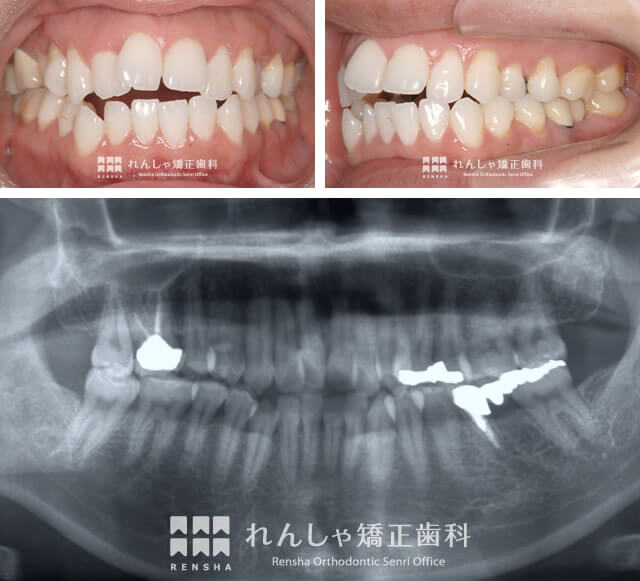

大人の矯正症例 C.Nさん治療記録

C.Nさんの治療概要

このままでは物を噛むことができなくなるかも…そんな危機感から、矯正治療を決意される

前突した前歯は下前歯とズレが生じており、うまく噛むことができません。CNさんの場合、左下奥歯はむし歯治療で、一部の歯根を何とか残す処置を受けられていました。

ただ矯正治療開始前の時点では、わずかに残った歯根もダメになりかけていた状態。C.Nさん自身も、「このままでは、前歯だけでなく奥歯も噛めなくなってしまう」という危機感をお持ちでした。このような噛み合わせの問題もあって、C.Nさんは矯正治療に踏み切られた訳です。

| 主訴 | 上前歯の前突 |

|---|---|

| 診断名 | Angle Class II 上顎前突 |

| 初診時年齢 | 35歳8か月 |

| 装置名 | マルチブラケット装置 |

| 抜歯非抜歯 | 上下顎左右第一小臼歯と下顎左側第一大臼歯の抜歯(合計5本) |

| 治療期間 | 2年8か月 |

| 費用の目安 | 約85万円+消費税(検査料金、都度の処置費用等も合わせた総額) |

| リスク副作用 | 歯の移動に伴う軽微な歯根吸収、歯槽骨吸収、歯肉退縮(本症例では軽度の歯肉退縮を認めた)、矯正器具装着中のカリエスリスク増大(本症例ではカリエス発生無し) |